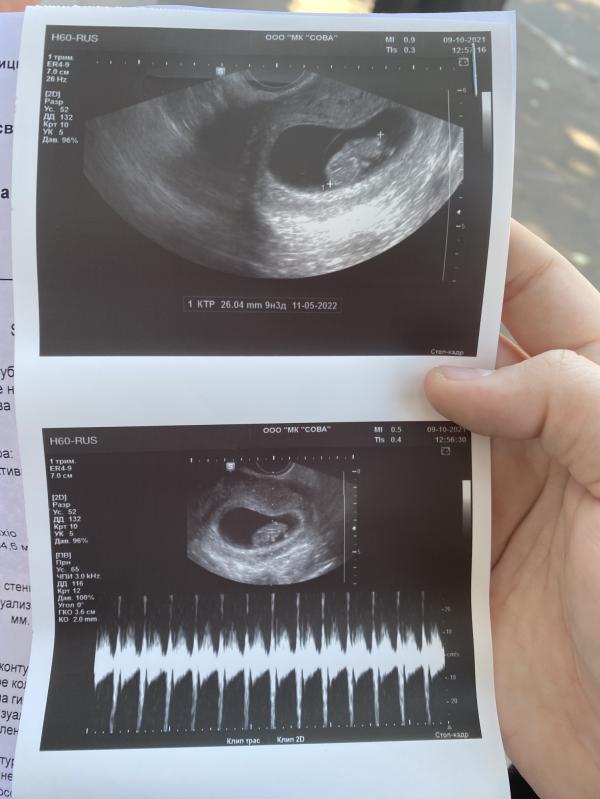

Ходила на УЗИ посмотреть всё ли хорошо с малышом.. поставили гипертонус передней стенки, у кого было так это опасно или нет? Врач сказала что может быть угроза прерывания или они всем так говорят с тонусом? Купила вчера магний буду пить😌очень переживаю😞